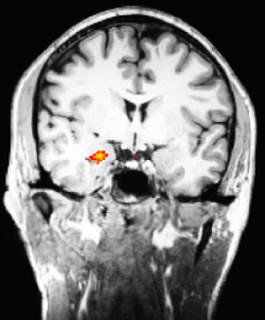

Research is in: Meditation works!

Meditation appears to produce enduring changes in emotional processing in the brain

Meditation appears to produce enduring changes in emotional processing in the brainThe good folks at Mass General Hospital (MGH), Boston University and other research institutions have shown conclusively in a research setting, for the first time, that an 8-week meditation program affected brain function in a positive way even when the subjects were not meditating. The amygdala (our crisis response center) was positively affected by their modest practice. Highly recommended reading!(Click on the title to go right to the article.)